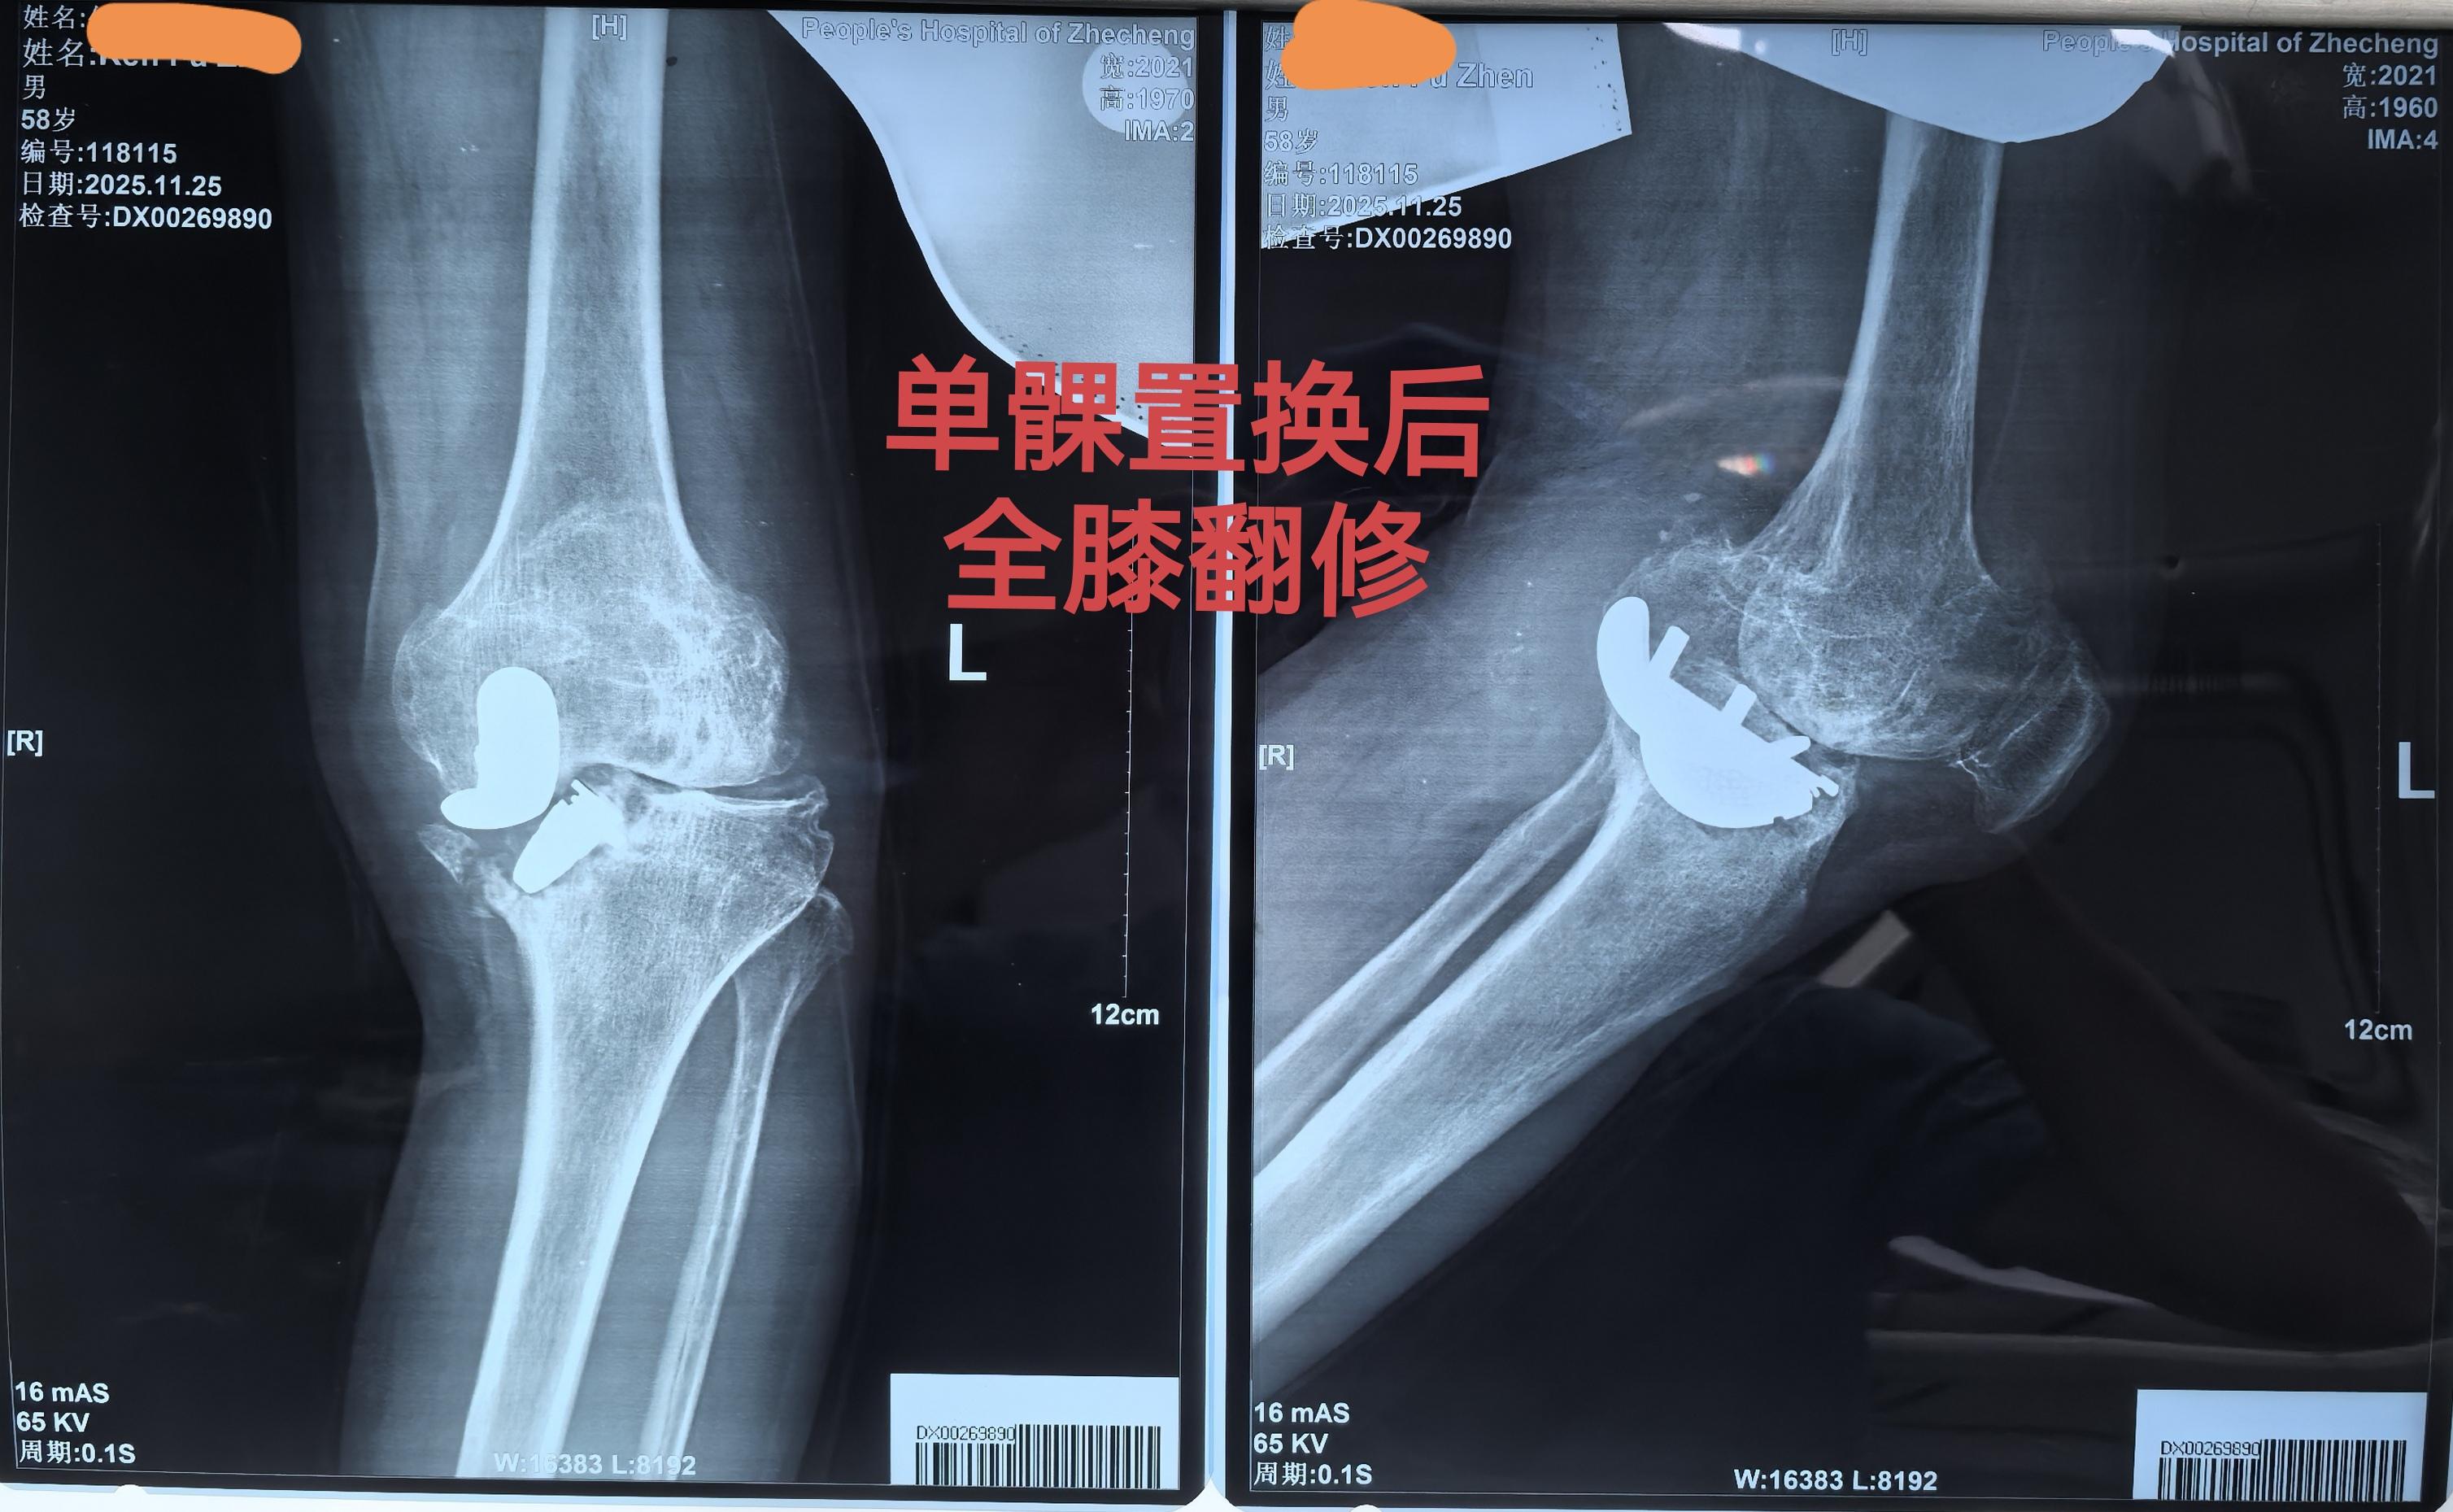

单髁置换术后全膝翻修。单髁置换术后假体松动,双侧全膝翻修。还是那句话...